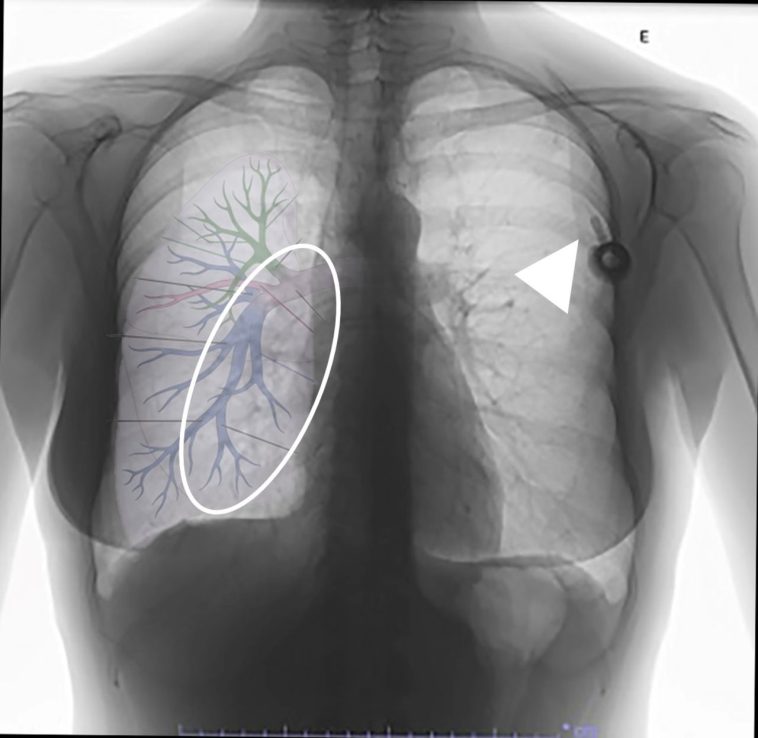

During the operation, a common iliac vein injury emerged as a result of the disc curettage process—a step that, under normal circumstances, requires precise handling and careful judgement. In an effort to control the bleeding from a small venous tear, a suction tube enhanced with a Nelaton cover was employed. This makeshift device, typically used to protect suction tips from high-speed drills, ultimately became dislodged. It then migrated through the vascular system, resulting in a pulmonary artery embolism that required immediate surgical removal by a team of thoracic surgeons.

Risks of Vascular Injury in Lumbar Procedures

Vascular injury during lumbar surgery is a full-of-problems domain. Although such injuries are rare, they are laden with the potential for serious, sometimes overwhelming, consequences. Recognizing the dangerous proximity of major blood vessels such as the common iliac vein and the aorta is fundamental to understanding these risks.

Close Proximity of Vital Vessels

Surgical interventions at the L5/S1 level encounter the close vicinity of the common iliac artery, the common iliac vein, and even the aorta. This proximity means that even minor unintentional movements or increased pressure during the procedure can result in significant vascular damage. The following points highlight why this region is particularly risky:

Complications Arising from Vascular Injuries

The complications that arise from vascular injuries during lumbar surgery are not limited to severe blood loss. They can also include thromboembolic events such as deep vein thrombosis and pulmonary embolism. Some examples of related complications include:

- Hemorrhage: Significant bleeding due to vessel laceration may require rapid intervention.

- Clot Formation: When a blood vessel is compromised, there is potential for the development of clots that can migrate and cause additional issues.

- Organ Damage: In cases where emboli travel to the lungs, respiratory function can be impaired, necessitating further surgical intervention.